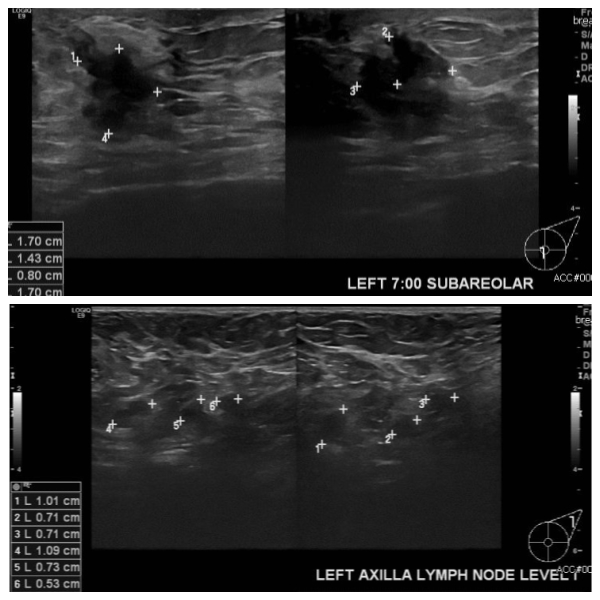

상기 환자 좌측 만져지는 멍우리로 내원하신 30대 여성분으로  좌측 7시 방향 유두

밑 만져지는 멍우리 조직검사 시행하여 좌측 침윤성 유방암 진단 되었고, 좌측 겨드랑이

림프절비대 세포검사 시행하여 전이암 진단 되었습니다.